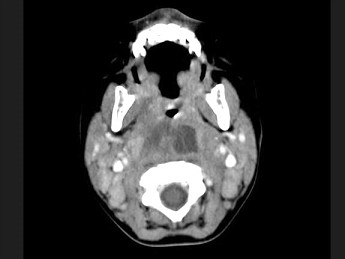

[多选题] 10个月大的婴儿,发热,曾患中耳炎,CT扫描如图所示,正确的描述或诊断是()A . 咽后壁软组织肿胀B . 其内密度不均C . 颈椎骨质未见明显异常D . 咽后壁脓肿E . 咽后壁寒性脓肿